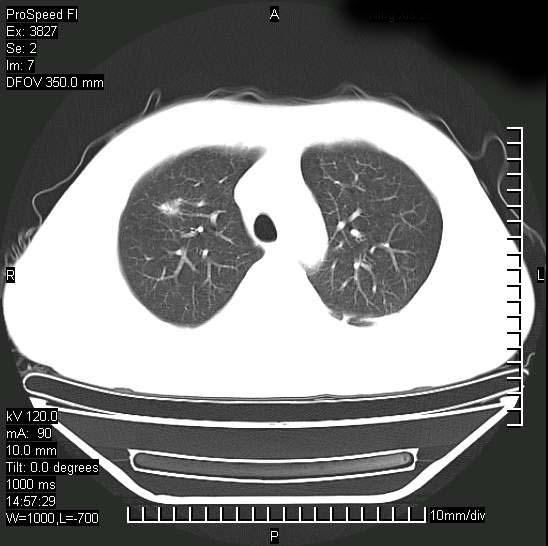

男性,一月前出现右侧肋区疼痛,较剧烈,干咳,无发热,自诉使用抗炎药后缓解,几天前又出现左侧剧烈疼痛,

发热,体温38。9,今天ct,考虑左侧包裹性脓胸,胸腔积液,右上中肺小斑片影,结核/炎症?胸水未见恶性细胞。